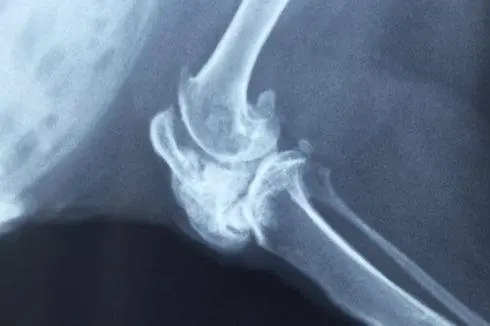

1.1.X線所見為骨內(nèi)的溶骨性病變,可有鈣鹽沉積,大部分腫瘤生長(zhǎng)緩慢,少數(shù)生長(zhǎng)迅速。在骺干骺端,腫瘤為偏心性;在骨干,則位于骨干的中心。

1.2.中心性軟骨肉瘤可表現(xiàn)為邊界模糊的溶骨,有或無皮質(zhì)骨中斷,由于軟骨傾向于鈣化和骨化,腫瘤內(nèi)可出現(xiàn)不透X線區(qū),鈣化經(jīng)常發(fā)生在軟骨小葉的周圍,無一定結(jié)構(gòu),其特征為不規(guī)則的霧狀顆粒、結(jié)節(jié)或不透X線的環(huán)。

1.3.由于瘤壁骨嵴,腫瘤可產(chǎn)生泡狀或面包屑樣外觀。如鈣化致密,腫瘤可呈不透X線的金屬樣。如腫瘤浸潤(rùn)到松質(zhì)骨的髓腔而未破壞骨小梁時(shí),鈣沉積和反應(yīng)性骨增生可呈不透X線均勻一致的海綿骨樣。如腫瘤浸潤(rùn)松質(zhì)骨未破壞骨小梁且無鈣化時(shí),骨內(nèi)的腫瘤部分可不顯影,在這種情況下,如果不借助骨掃描、CT和MRI,中心性軟骨肉瘤的診斷困難且晚。

分化良好的中心性軟骨肉瘤鈣化多,而Ⅲ級(jí)中心性軟骨肉瘤及反分化中心性軟骨肉瘤鈣化少且粘液區(qū)多。

皮質(zhì)骨可以很薄,內(nèi)部呈扇貝狀,在一些區(qū)域可有中斷。有時(shí)由于腫瘤膨脹緩慢,皮質(zhì)骨發(fā)生增生,可顯得增厚。這種增厚的皮質(zhì)骨表現(xiàn)相當(dāng)?shù)湫?,表明其已被腫瘤所浸潤(rùn)。

中心性軟骨肉瘤傾向于向阻力較小的地方擴(kuò)張,如骨干的髓腔。在幾乎一半的病例中,放射影像顯示腫瘤侵犯整個(gè)長(zhǎng)骨的1/3、1/2或更多,但在腫瘤早期,影像上可能無顯示。這個(gè)特點(diǎn)很重要,否則手術(shù)方案可能不恰當(dāng),切除緣可能不夠,于骨干切除或截肢術(shù)后殘肢處腫瘤可復(fù)發(fā),為避免發(fā)生,須在術(shù)前通過骨掃描、CT和MRI來確定腫瘤在髓腔內(nèi)的范圍。

在侵襲性較強(qiáng)的病例中,中心性軟骨肉瘤早期即可有廣泛的皮質(zhì)中斷,較大的軟組織腫塊,侵入軟組織中的瘤塊鈣化不明顯。受浸潤(rùn)被頂起的骨膜可以反應(yīng)性地產(chǎn)生薄的、稍不透X線的帶,垂直于皮質(zhì),但從不見在骨肉瘤中典型的牙刷影像以及Codman三角。